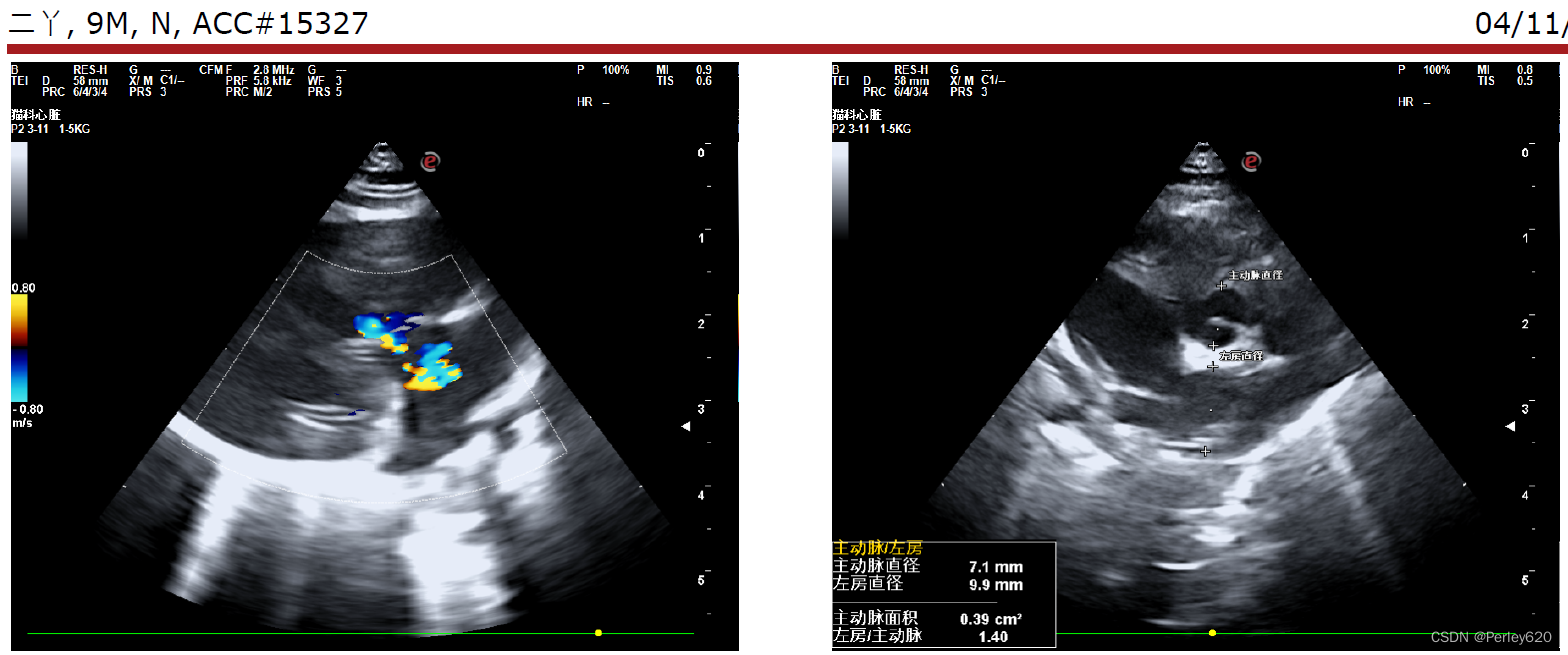

然后给她拍X光片,给她做彩超看心脏,宠物医院的院长看了半天,也没能确定是什么问题,她觉得是心脏左心室隔膜缺损,但没法给定论。

我们就去了宠物医院的总院,找了总院的院长做进一步的检查,最终是重度肺高压,就是很严重的一种病。

诊断的B超图